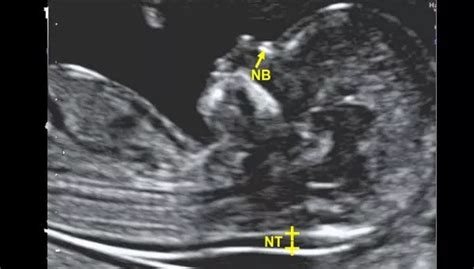

- Ecografia fetale: Oltre alla misurazione dello spessore della translucenza nucale - la raccolta di liquido retronucale presente in tutti i feti tra 11 e 13 settimane, ma che risulta aumentata nell'80% dei feti affetti da Sindrome di Down - l'ecografia permette anche la valutazione di altri parametri di crescita fetale e, in molti casi, la ricerca della presenza dell’osso nasale. La sua assenza o ipoplasia (sviluppo incompleto) può essere un ulteriore indicatore di rischio per alcune anomalie cromosomiche.

L'esame richiede l'uso di apparecchiature ecografiche di alta tecnologia, capaci di fornire immagini chiare e dettagliate del feto in una fase così precoce dello sviluppo. Durante l’esame, il medico ginecologo o l’ecografista specializzato si concentra non solo sulla misurazione dello spessore della translucenza nucale, ma valuta anche l’anatomia fetale ecograficamente indagabile. Questo include la verifica della presenza dell’osso nasale e di altri indicatori morfologici utili a individuare eventuali anomalie cromosomiche o strutturali.